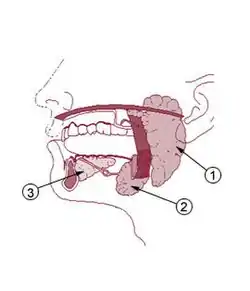

Stone formation occurs most commonly in the submandibular gland for several reasons. The concentration of calcium in saliva produced by the submandibular gland is twice that of the saliva produced by the parotid gland.[3] The submandibular gland saliva is also relatively alkaline and mucous. The submandibular duct (Wharton's duct) is long, meaning that saliva secretions must travel further before being discharged into the mouth.[3] The duct possesses two bends, the first at the posterior border of the mylohyoid muscle and the second near the duct orifice.[3] The flow of saliva from the submandibular gland is often against gravity due to variations in the location of the duct orifice.[3] The orifice itself is smaller than that of the parotid.[3] These factors all promote slowing and stasis of saliva in the submandibular duct, making the formation of an obstruction with subsequent calcification more likely.